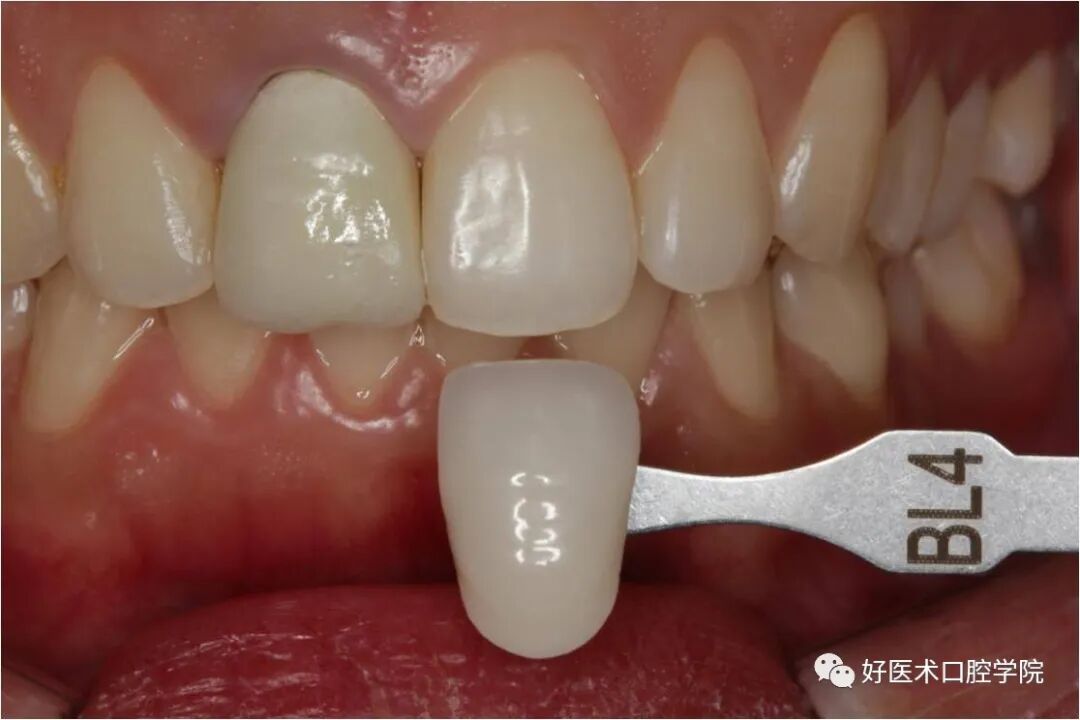

烤瓷牙颜色拍照三合一

烤瓷颜色做的色差大了再拍照片要做到三合一,(邻牙、烤瓷牙、比色板)这样技工在改色的时候才能做得更好。